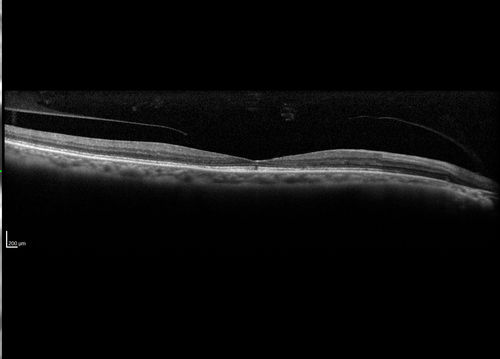

Cone Dystrophy - Autosomal Recessive

74 year old man with 20/25 vision OD and subtle bull's eye on FAF. Left eye is 20/200 with atrophy of the outer retina centrally